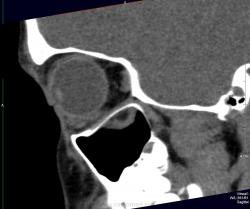

Отломок напоминает открытую дверцу, в которую вываливается нижняя прямая мышца и клетчатка. Бывает, что такая "дверца" захлопывается и ущемляет содержимое орбиты. Тут нужен зоркий глаз и знание клиники, так как сам перелом можно уже и не увидеть, отломок встал на место.

Глазное яблоко, стало быть, уцелело? Что же пролабирует в верхнечелюстную пазуху?

Зрение в порядке за исключением "пустяка" диплопии. Почему называется взрывным переломом? Вероятно потому, что перелом не от прямого удара по кости, иначе ломался бы край орибы. Ломается тонкое место в дне орбиты от резко повышения давления в орбите в результате прямого удара. Американцы приводят как пример типичный механизм прямого удара бейсбольным мячом. Как ни странно, медиальная стенка ломается реже, и еще реже верхняя стенка.

Вы правы, Валентин Львович, этот червячок на фоне темной жировой клетчатки орбиты нижняя прямая мышца. А в левой гайморовой пазухе случайная находка, видимо полип, клиники нет.